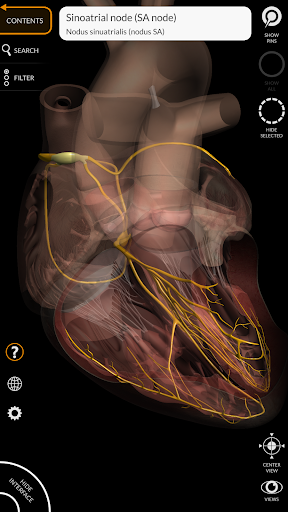

Các mô hình giải phẫu 3D đặc biệt chi tiết và có kết cấu lên đến độ phân giải 4k.

MÔ HÌNH GIẢI PHẪU 3D

• Hệ thống tim mạch

• Hệ thống thần kinh

• Chức năng trong suốt

• Bằng cách chọn một mô hình hoặc một ghim, thuật ngữ giải phẫu liên quan sẽ hiển thị